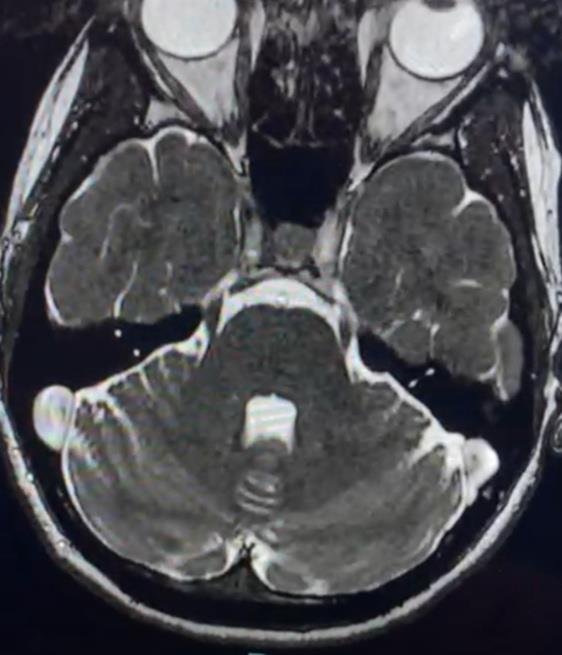

La causa más frecuente es la neuralgia del trigémino clásica, producida por la compresión del nervio trigémino por una rama arterial, habitualmente la arteria cerebelosa superior. Esta compresión suele localizarse a pocos milímetros de la salida del nervio del tronco del encéfalo. El latido arterial continuo sobre el nervio provoca una degeneración progresiva de su vaina protectora, lo que da lugar a la aparición de las crisis dolorosas.